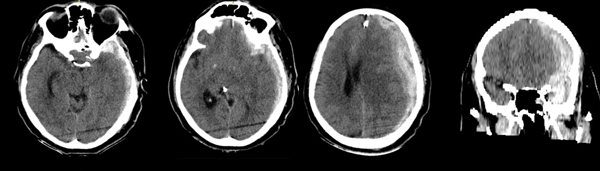

Ingresa por guardia por caída de propia altura, de la cual no se obtienen detalles por no haber estado acompañado en ese momento y no poder el paciente describir el evento con precisión. Se constatan signos menores de trauma (ligero cefalohematoma), lúcido y sin foco agregado. Seis horas después presenta rápido deterioro del sensorio, con Glasgow 12/15; se realiza TC que evidencia Hematoma Subdural Agudo mayor de 20 mm de espesor con desviación de línea media de 16mm y signos de herniación. El contenido heterogéneo del hematoma con signos de “jet” confirman la actividad del mismo. No se evidencian otras lesiones a nivel de parénquima (Figura 1). En su retorno a la sala de urgencias presentó evento convulsivo tónico-clónico asociado a anisocoria izquierda.

Figura 1. TC sin contraste al momento de su primer deterioro neurológico.